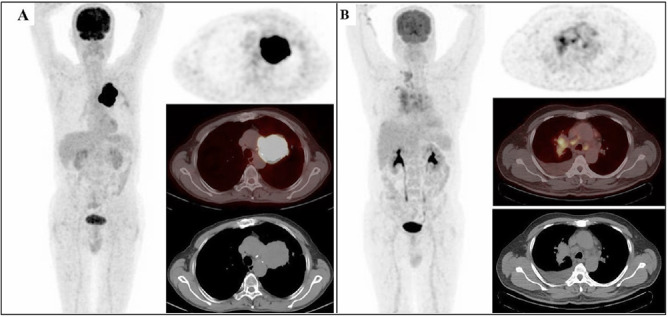

Methods: The 18F-FDG positron emission tomography/computed tomography images and mass lesion metabolism standard uptake value maximum (SUVmax) results of the patients were evaluated. Glucose transporter protein-1 (GLUT-1)-XbaI G>T (rs2754218) and HaeIII T>C (rs1385129) polymorphisms and their effects on 18F-FDG uptake rates were investigated using DNA obtained from peripheral blood.

Results: When the Xbal G>T genotype distribution of the patients was examined, the Xbal G/G genotype was found to be 87%, the Xbal G/T genotype 12%. The XbaI T/T phenotype was detected in only one patient (1%). In the HaeIII T>C genotype distribution, the HaeIII C/C genotype was found as 54%, the HaeIII T/C genotype as 31%, and the HaeIII T/T genotype as 15%. When the Xbal and HaeIII genotypes were examined together, the number of polymorphic genotypes was significantly higher in the lung and bronchial tumor groups compared to other cancer types.

Conclusion: The presence of polymorphism in at least one of the two gene regions, in the lung-bronchial tumor group and the high SUVmax value in this patient group, may indicate a change in the involvement rates.